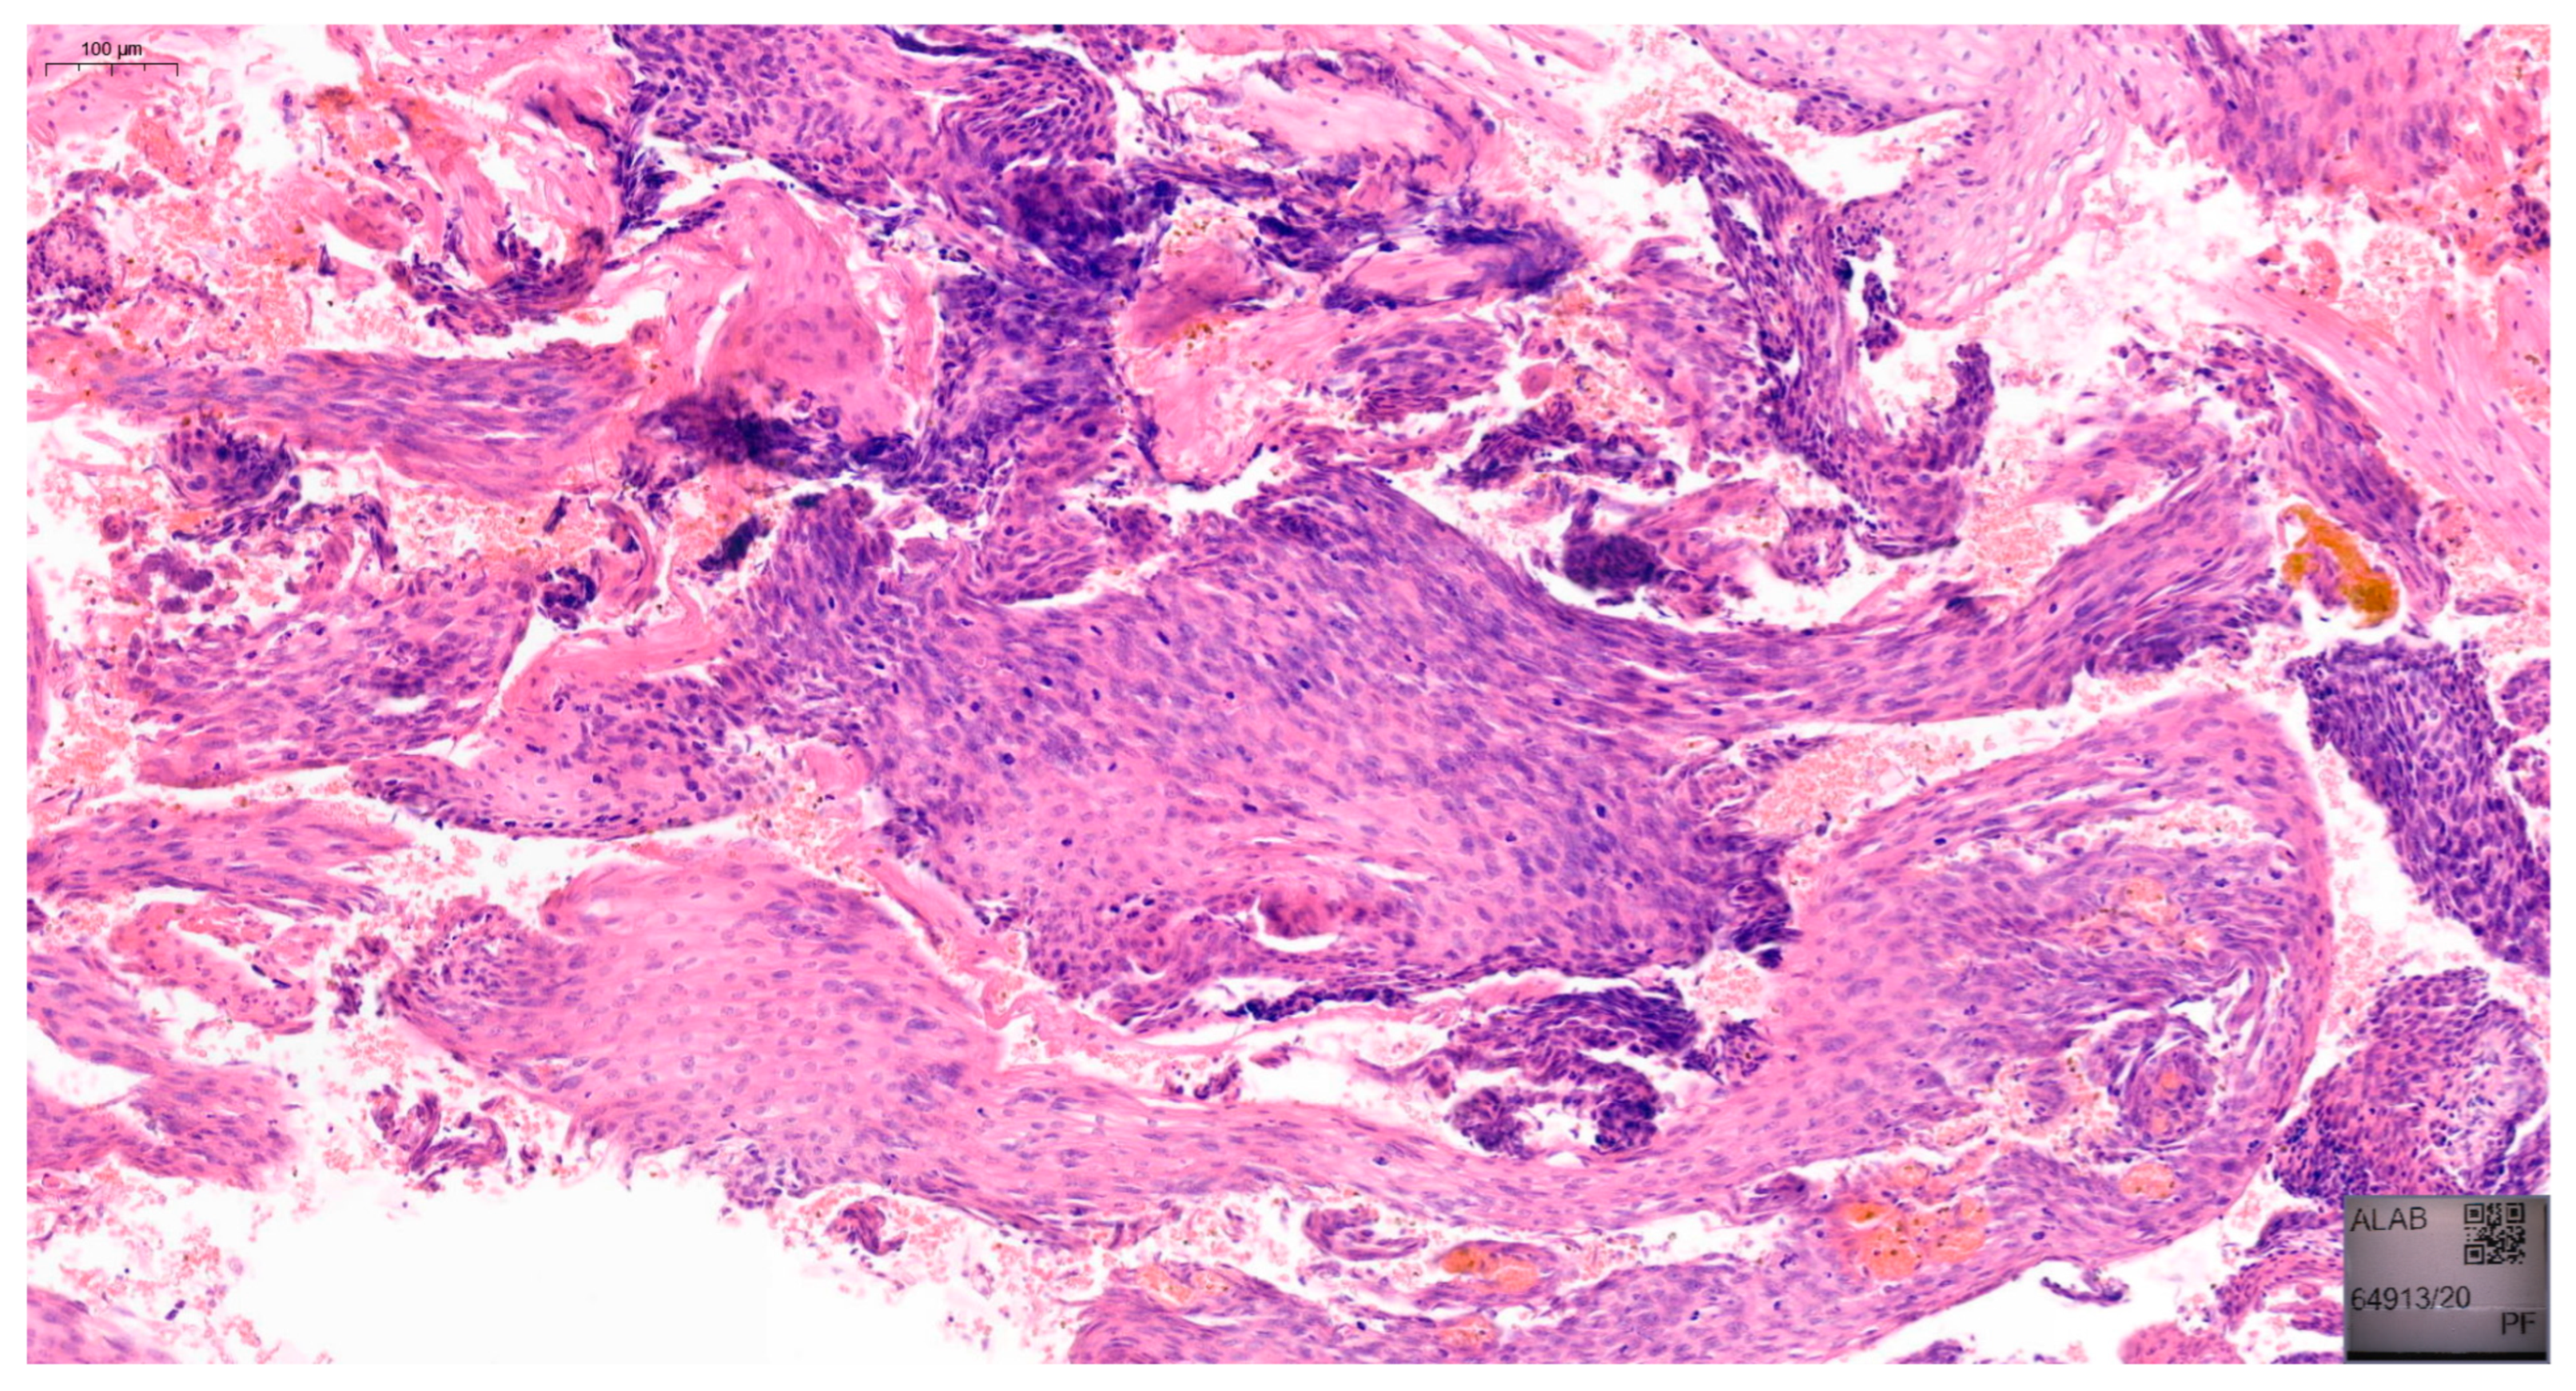

Furthermore, in approximately 75% of women, VaIN coexists with cervical or vulvar cancer [17]. The 2020 World Health Organization (WHO) classification distinguishes between low-grade squamous intraepithelial lesions (LSIL), which include VaIN 1, and high-grade squamous intraepithelial lesions (HSIL), including VaIN 2 and VaIN 3 [18]. Examples of VaIN 1 and VaIN 2+ lesions in patients from our cohort are shown in Figure 1 and Figure 2, respectively. Numerous studies have reported the risk of HSIL progressing to vaginal cancer ranging from 2% to 12% [19,20]. VaIN is treated in several ways, including CO2 laser ablation, photodynamic therapy, topical imiquimod, excisional surgery, electrocoagulation diathermy, or brachytherapy [9,21,22]. Therefore, VaIN is still a major diagnostic and therapeutic challenge, and further research is needed.

Figure 1. Histopathological image of VaIN 1, showing mild nuclear atypia confined to the lower third of the vaginal squamous epithelium, without evidence of invasion. Hematoxylin and eosin stain (H&E), original magnification ×200.

Figure 2. Histopathological image of VaIN 2/3, demonstrating marked nuclear pleomorphism and loss of maturation involving more than two-thirds of the epithelial thickness. Hematoxylin and eosin stain (H&E), original magnification ×200.